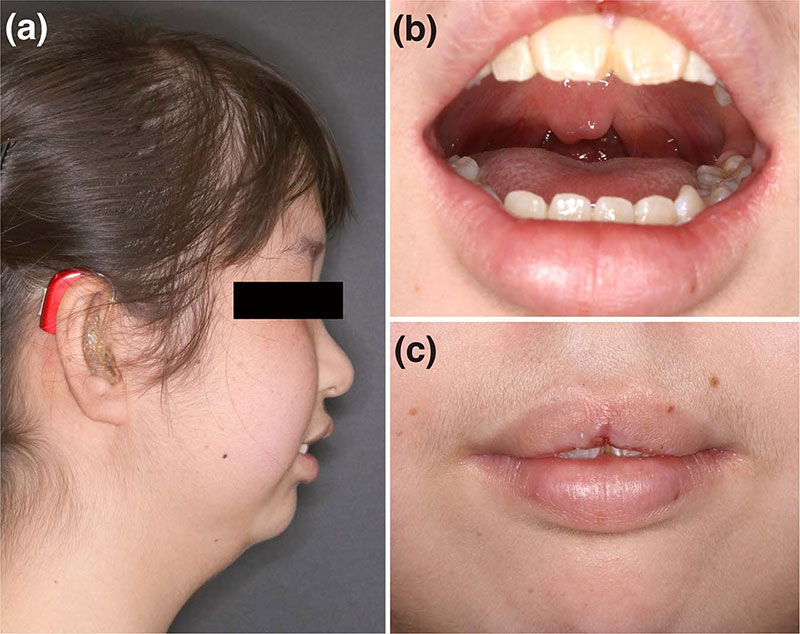

اورجت یا جلو بودن دندان های فک بالا به حالتی گفته می شود که دندان های جلویی فک بالا خیلی جلوتر از دندان های فک پایین هستند.این وضعیت علاوه بر تاثیر در ظاهر بر عملکرد جویدن نیز اختلال ایجاد می کند.

در برخی موارد، دندان های بالایی به صورت صحیح روی دندان های پایینی قرار نمی گیرند و یک شکاف افقی بین دندان های جلویی بالا و دندان های جلویی پایین ایجاد می شود به این حالت اورجت شدید گفته می شود. در این وضعیت، دندان های جلویی بالا ممکن است خیلی جلوتر یا خیلی عقب تر از دندان های جلویی پایین قرار گیرند. این شکاف افقی باعث بیشتر در معرض دید قرار گرفتن دندان های بالا نسبت به دندان های دیگر می شود که برخی افراد این وضعیت را به عنوان دندان خرگوشی توصیف می کنند.

جلو بودن فک بالا سبب تغییر در چهره بیمار می شود؟

جلو رفتن دندان های فک بالا (اورجت)، باعث برآمدگی لب بالایی فرد می شود و لب بالایی جلوتر از حالت طبیعی قرار می گیرد. این تغییرات در تناسب بین فک ها و دندان ها بر ظاهر کلی لبخند و چهره فرد تاثیر می گذارد.